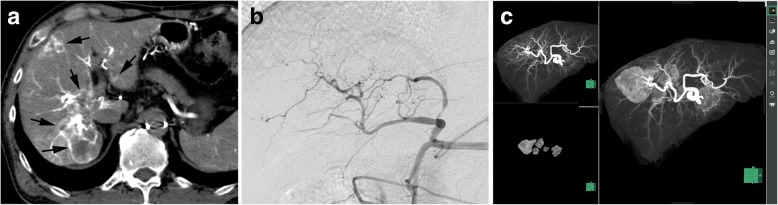

Fig. 1.

TACE navigation system by using a CT workstation. a. CT during contrast injection via the hepatic artery was obtained. Multiple metastases were seen in the right hepatic lobes (arrows). b. Hepatic angiography could not depict the tumors. c. maximum intensity projection (MIP) image of the hepatic artery and extraction of the tumors were individually created (left side). Fusion of these two images shows the tumor feeding branches of the tumors